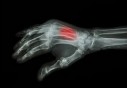

La Journée mondiale de l'ostéoporose est l'occasion de faire le point sur cette maladie qui touche une femme sur trois... mais qui concerne aussi les hommes.

L'ostéoporose peut en effet toucher femmes et hommes dès 30 ans, si ceux-ci ont un faible capital osseux (s'ils sont maigres) et des facteurs de risque qui accélèrent la perte osseuse : facteurs génétiques ou d'environnement, maladie (ostéomalacie, cancer des os, dystrophie osseuse) ou traitement susceptible d'entraîner une ostéoporose.

Les médecins pensent rarement à prescrire une ostéodensitométrie (un examen qui permet de mesurer la densité osseuse) aux hommes, pourtant, une fracture de la hanche sur trois concerne les hommes. Il existe des facteurs de risque typiquement masculins : la privation d'hormones androgènes chez les hommes qui ont été soignés pour un cancer de la prostate et l'usage de stéroïdes. Mais la carence en vitamine D et en calcium et le tabagisme sont également des risques masculins.

Effectivement, dans la majorité des cas, les os commencent à se fragiliser aux alentours de la cinquantaine. Après la ménopause, l'organisme produit moins d'œstrogènes, or ceux-ci agissent sur la formation de l'os "nouveau". Le déficit en hormones œstrogéniques constitue chez les femmes le facteur de risque d'ostéoporose le plus important. Il va entraîner un déséquilibre entre les phénomènes de construction et de destruction de l'os, au profit de la destruction. Mais, fort heureusement, toutes les femmes ménopausées ne vont pas développer systématiquement une ostéoporose.